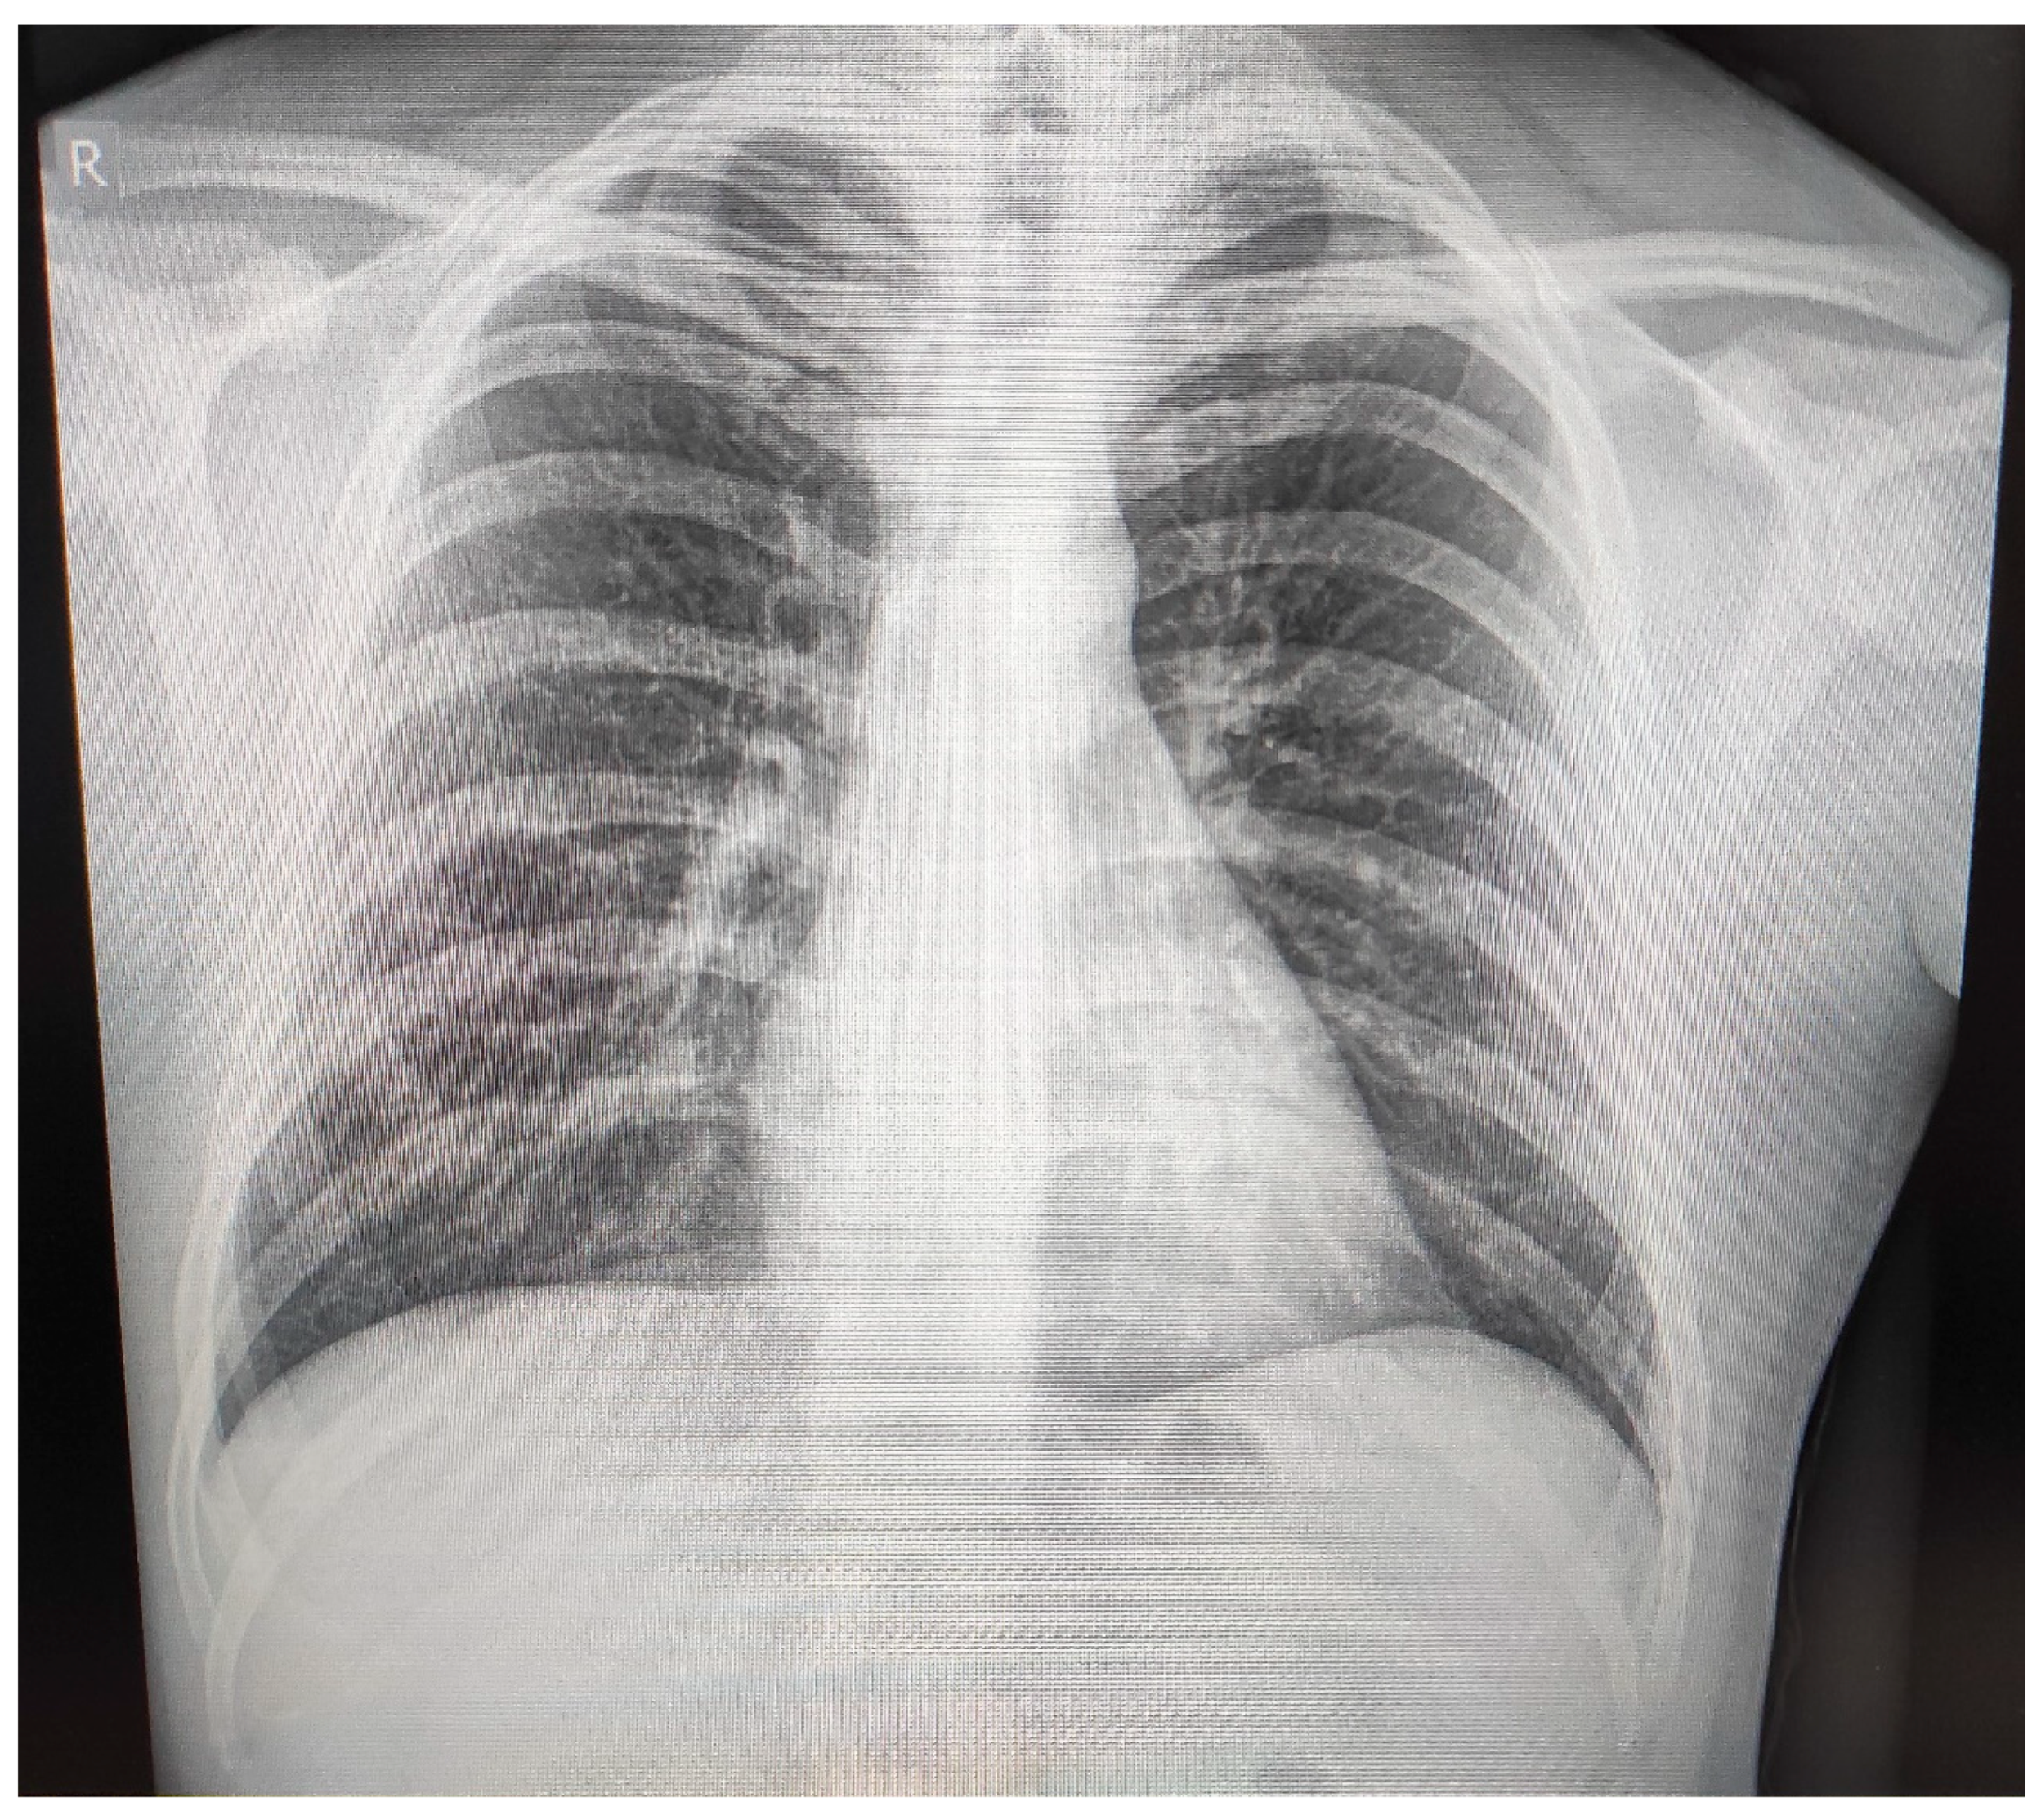

2. Case Report